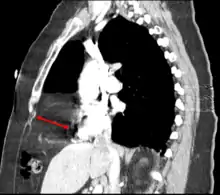

a)Posterolateral diaphragmatic hernia was discovered b) small bowel loops entering the thorax c) after reducing contents d)extreme left lung hypoplasia